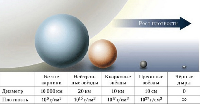

Мобильный рентгенаппарат + оцифровщик. Получение рентгеновского изображения на экране ноутбука. Вариант за 1,4 миллиона рублей под ключ.

Мобильный рентгенаппарат с печатью рентгенограмм на рентгеновской пленке. Цена 700000 рублей.